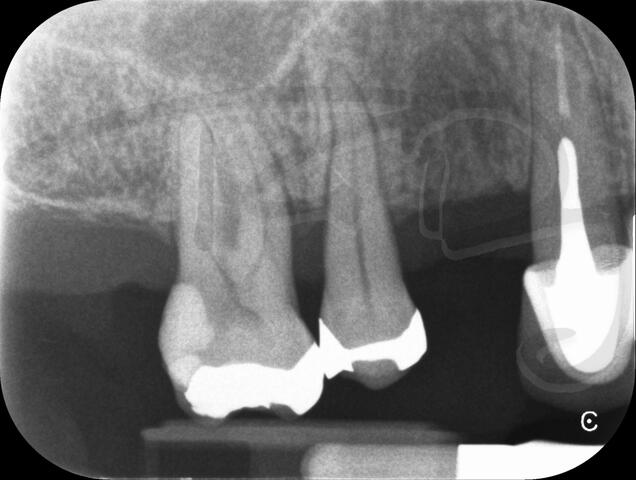

I really enjoy undertaking root canal treatments - rising to the challenge and helping people out of dental pain for the long term.I was privileged to be asked to speak at the 2016 BDA Conference, where I have a lecture about providing quality endodontic outcomes to patients, working as a generalist. Avoiding problems and pitfalls and maximising efficiency. One of the main matters that he covered was understanding that what is seen on plane radiography is utterly misleading and should not be the criteria by which a generalist continues treatment once it has been started.

At the 2016 BDA Conference, Thomas spoke about providing quality endodontic outcomes to patients, working as a generalist. Avoiding problems and pitfalls and maximising efficiency. One of the main matters that he covered was understanding that what is seen on plane radiography is utterly misleading and should not be the criteria by which a generalist continues treatment once it has been

started.